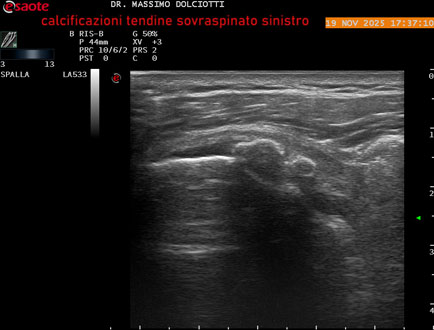

Ecografia del: 19/11/2025

Strumento: Esaote MyLab Eight

Sonda: Lineare Multifrequenza 3-13 MHz

Età Paziente: M 52 anni

Motivazione dell'esame: dolore alla spalla sinistra che peggiora con il freddo.

Commento all'esame: le immagini ed il video documentano il tendine sovraspinato sinistro disomogeneo per evidenza, in sede prossimale e mediale, di immagini iperecogene multiple, delle dimensioni di 5,8 mm - 6,1 mm - 4,6 mm da ricondurre a calcificazioni.

Conclusioni: calcificazioni del tendine sovraspinato sinistro (calcifications of the left supraspinatus tendon).